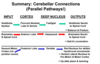

Summarise cerebellar connections in the cerebellum (so all the pathways in the cerebellum only)

What are the three main cerebellar outputs?

The regulation of balance, posture and gait ( this refers to how you walk).